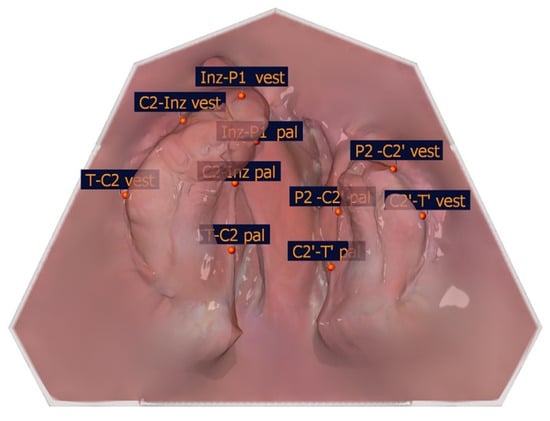

To identify the transversal landmarks, the large and small segments were divided into the subsegments (T-C2, C2-Inz, and Inz-P1 for the large segment and P2-C2′ and C2′-T′ for the small segment). The most vestibular and most palatal points in each section were determined (Table 2, Figure 5).

The large and small segments were divided into subsegments to identify the transversal landmarks (T-C2, C2-Inz, and Inz-P1 for the large segment and P2-C2′ and C2′-T′for the small segment). The most vestibular and most palatal points in each section were determined. For the segmental width measurements, the greatest distance perpendicular to the length measuring sections of the partial jaw segments defines the greatest width of the jaw segments. The segment width measurements are shown in Table 4, and an exemplar is shown in Figure 9.

Figure 5. Illustration of the segmental width measuring measurement points of the partial jaw segments. The segmental width measurement points and their description are presented in Table 2.